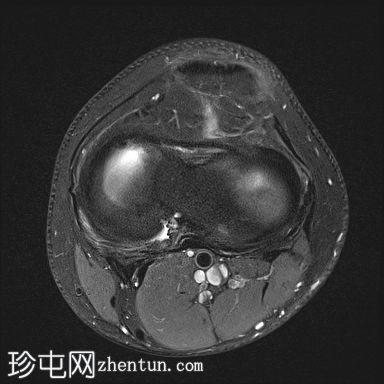

轴向PD

脂肪饱和度

股骨内侧髁发育不全

胫骨髁间棘发育不全

腓骨头发育不全

前交叉韧带(ACL)和后交叉韧带(PCL)发育不全

髌腱延长,低位插入。

腘绳肌腱起源异常

外侧胫骨半月板韧带增厚;与外侧韧带(LCL)连接

术后可能出现股四头肌腱改变

本病例展示了腓骨半肢畸形(I型)的特征性表现。然而,腓骨半肢畸形可能伴有多种其他异常及异常组合,包括本例中的十字韧带发育不良。本文所述结果仅代表该疾病的一种可能变体。